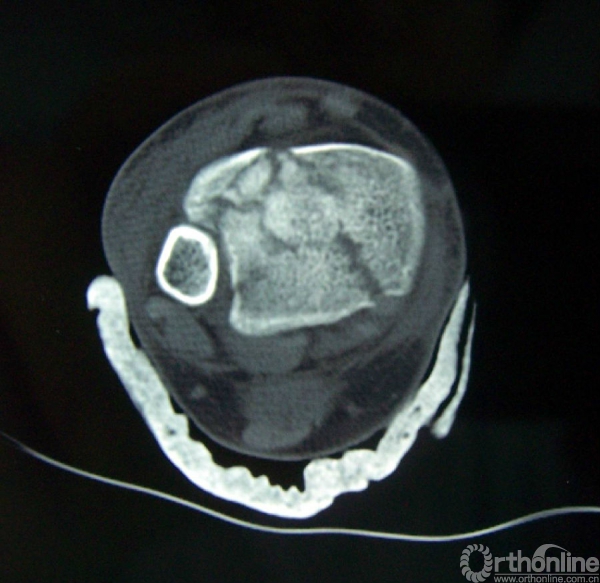

3b.水平面CT扫描可见属于内侧柱的内踝骨折块、属于中柱的前外侧和后唇骨折块;

4b.CT水平面扫面及表面重建示内侧柱及中柱有明显的骨折;